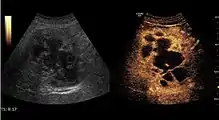

2D ultrasound, Doppler ultrasound and especially CEUS can play an important role in pretherapeutic staging, particularly when sectional imaging investigations (CT, MRI) provide uncertain results or are contraindicated. During the interventional procedure, ultrasound allows guidance of the needle into the tumor. CEUS allows guidance in areas of viable tissue and avoids intratumoral necrotic areas. CEUS also allows assessment of therapeutic effect immediately post-procedure (with the possibility of reintervention in case of partial response) . To accurately assess the effectiveness of treatment it is mandatory to compare the tumor diameter before therapy with the ablation area. The volume of damaged tissue must be higher than the initial tumor volume. CEUS appearance is that of central nonenhanced area showing a peripheral homogeneous hyperenhanced rim due to post-procedure inflammation. 24 hours after the procedure the inflammatory peripheral rim is thinning and the necrotic area appears larger than at the previous examination. Thus, a possible residual tumor may appear more evident. Residual tumor has poorly defined edges, irregular shape, and the tumor diameter is unchanged. Residual tumor tissue is evidenced at the periphery of the tumor as an eccentric area behaving as the original tumor at CEUS examination, with arterial hyperenhancement and portal and late wash-out. Ultrasound examination 24 hours after the procedure, including CEUS, can show apart from the character of the lesion any potential post-intervention complications (e.g. active bleeding).

In the first days after RFA both CEUS and spiral CT have low sensitivity in assessing therapeutic efficacy. CT sensitivity 24 hours post-therapy is reported to be even lower than CEUS. Difficulties in CEUS examination result from post-lesion hyperemia, presence of intratumoral air, ultrasound limitations (too deep lesion or the presence of fatty liver) or lack of patient's cooperation (immediately after therapy). For this reasons contrast imaging (CT or CEUS) control should be performed one month after ablation to confirm the result of the therapy.

Local recurrence is defined as recurrence of a hyperenhanced area at tumor periphery in the arterial phase, with portal and late wash-out. Sometimes, especially for HCC treated by alcoholization (PEI) hyperenhanced septa or vessels can be shown inside the lesion.